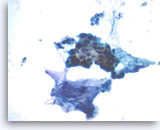

Ductal adenocarcinoma #1,

Pancreas FNA, Direct Smear.

The tumor cells have prominent intracytoplasmic vacuoles, irregular nuclear contours, vesicular chromatin and are arranged in three-dimensional clusters.

40X